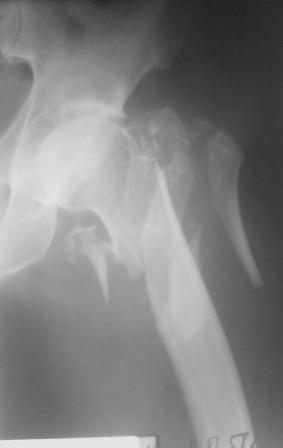

Чрезвертельный перелом бедра

Уважаемые коллеги. В наше отделение поступил пациент, мужчина 60 лет, с закрытым оскольчатым чрезвертельным переломом левого бедра.

Хотелось бы знать Ваши соображения по поводу лечения данного перелома. Снимки прилагаю.